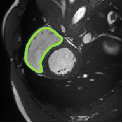

Despite their outstanding accuracy, semi-supervised segmentation methods based on deep neural networks can still yield predictions that are considered anatomically impossible by clinicians, for instance, containing holes or disconnected regions. To solve this problem, we present a Context-aware Virtual Adversarial Training (CaVAT) method for generating anatomically plausible segmentation. Unlike approaches focusing solely on accuracy, our method also considers complex topological constraints like connectivity which cannot be easily modeled in a differentiable loss function. We use adversarial training to generate examples violating the constraints, so the network can learn to avoid making such incorrect predictions on new examples, and employ the Reinforce algorithm to handle non-differentiable segmentation constraints. The proposed method offers a generic and efficient way to add any constraint on top of any segmentation network. Experiments on two clinically-relevant datasets show our method to produce segmentations that are both accurate and anatomically-plausible in terms of region connectivity.